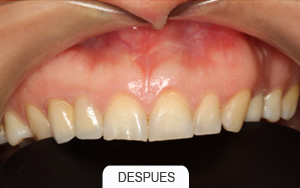

Casos Clínicos

Implantes dentales. Rehabilitaciones complejas